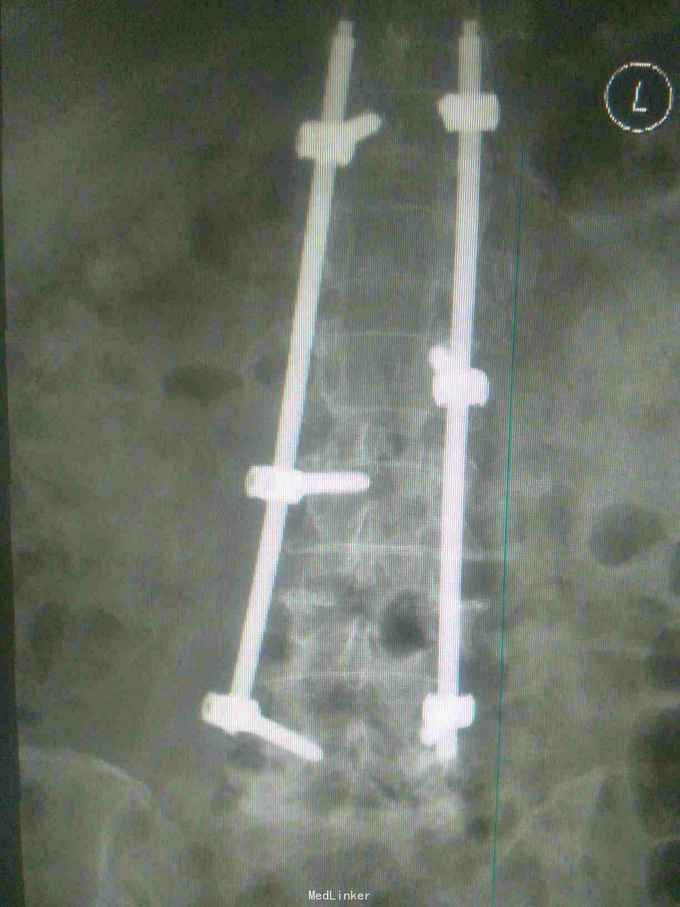

诊断腰1,腰4椎体爆裂性骨折,腰5椎体压缩性骨折,脊髓圆锥损伤双下肢截瘫。患者入院后48小时内行了腰椎后路腰1.4椎体切开复位椎弓根钉内固定,腰1椎板切除,椎管扩大成形,横突间植骨融合术。

1.大家看看这个钉棒打得怎么样,欢迎拍砖,2.由于我院因材料没的问题有,急诊手术能力,影响脊髓损伤病人的手术疗效,,在没有内固定的前提下,一期先减压,二期上内固定,效果怎么样,请同行前辈多指导。